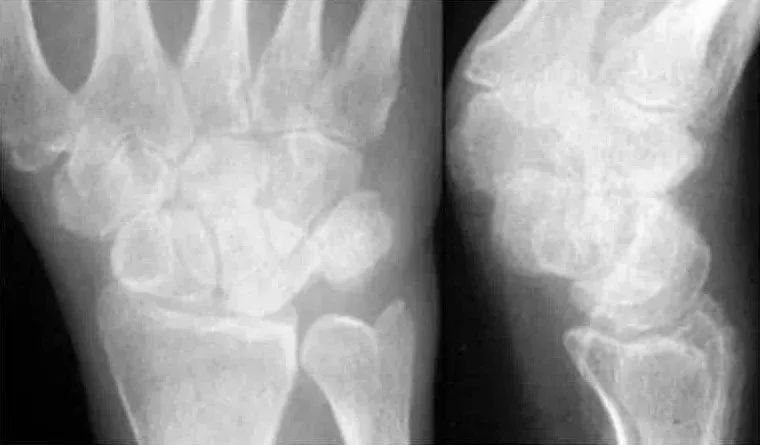

Case 分析

舟骨-大多角骨-小多角骨关节(STT关节)、第1腕掌关节(CMC1关节)严重骨关节病伴半脱位,掌骨弧线正常、平行关系存在。舟骨变长提示其向背侧倾斜。

侧位片示月骨也向背侧倾斜,近排腕骨作为一个整体移动,所以不存在脱位。

最后诊断:无脱位DISI(背屈不稳)伴STT关节骨关节病及半脱位。